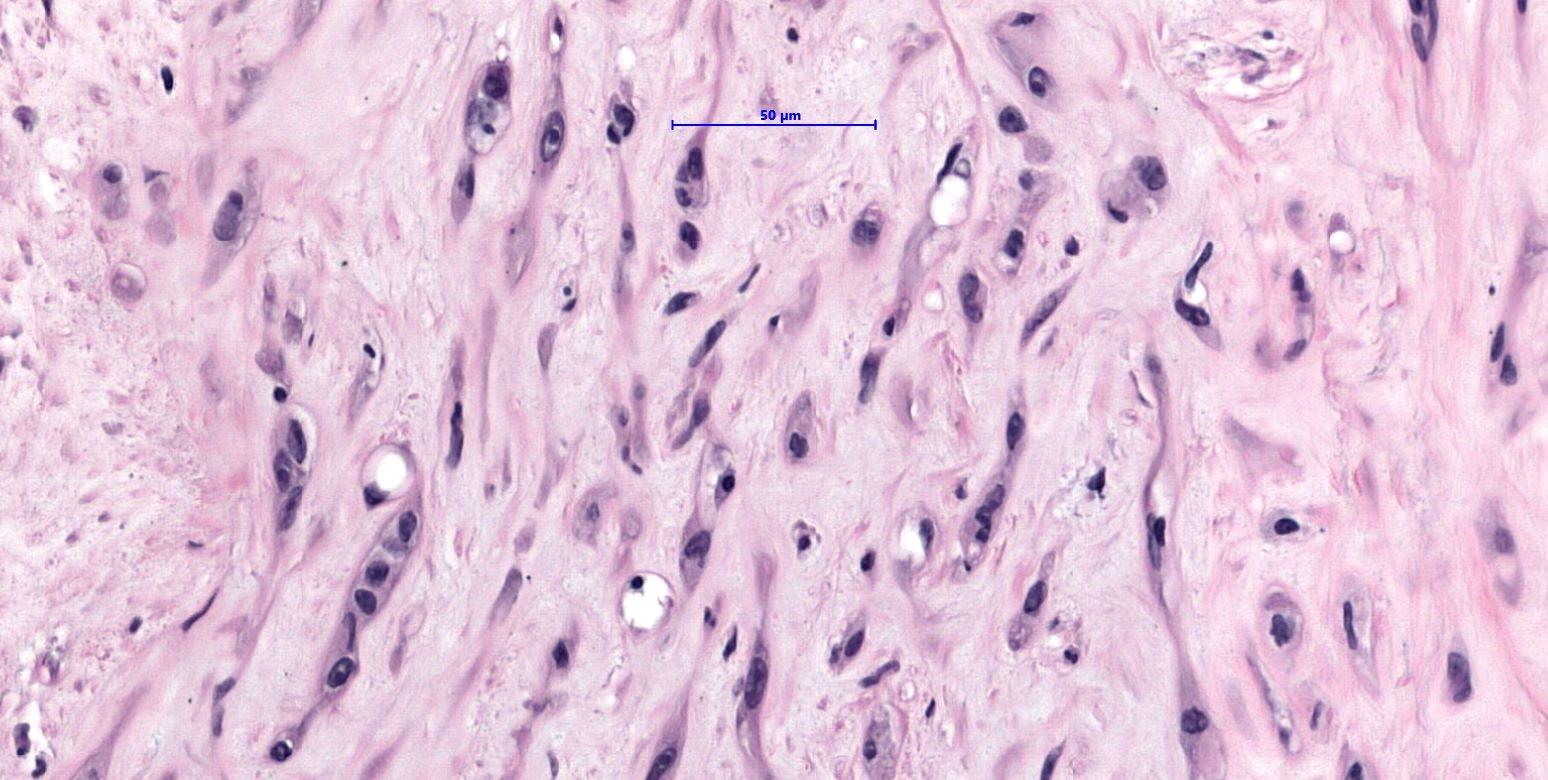

- WWTR1-CAMTA1 subtype (classic EHE):

- Cords, strands or small nests of large endothelial cells with abundant eosinophilic cytoplasm embedded in a myxohyaline stroma

- Tumor cells have vesicular, round to oval, sometimes indented nuclei

- Some tumor cells have intracytoplasmic, round, clear vacuoles representing small vascular lumina, which may contain erythrocytes

Microscopic (histologic) images